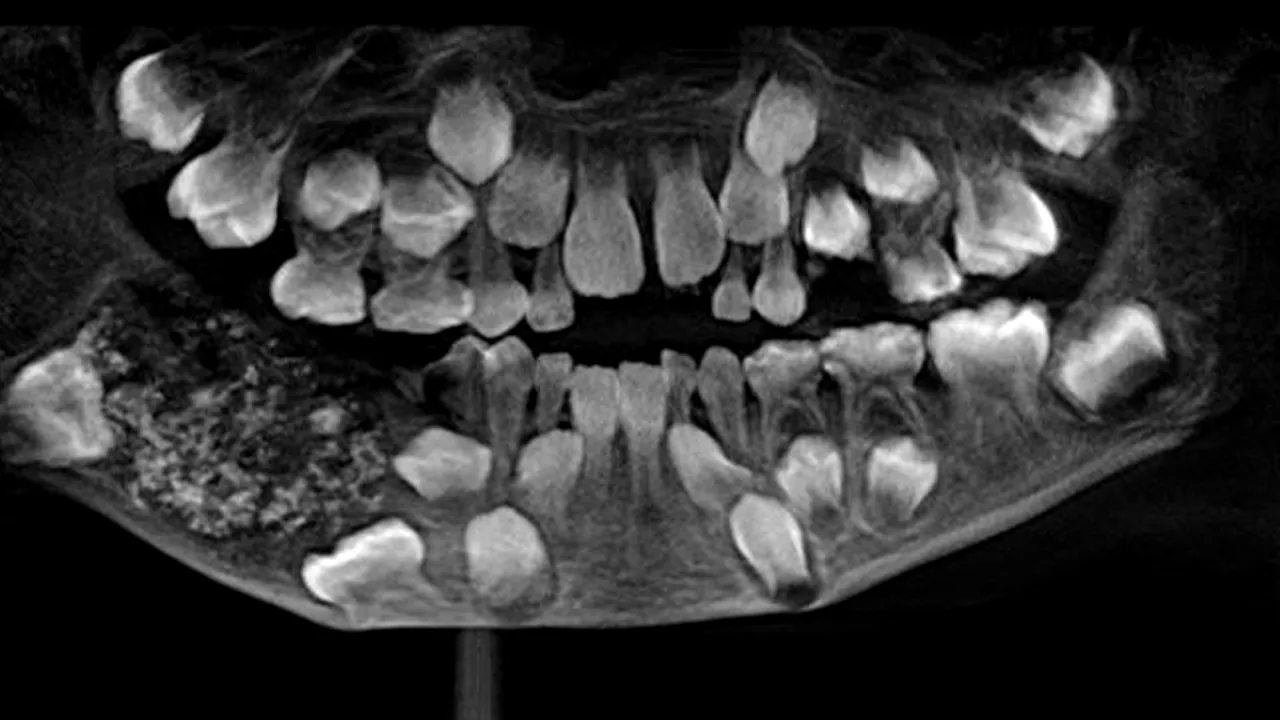

Caz medical neobișnuit în India. Unui băiețel de șapte ani i-au fost extrași 526 de dinți de dimensiuni cuprinse între 1 și 15 milimetri, după ce acesta s-a plâns de dureri insuportabile de maxilar.

După ce l-au supus razelor x, medicii au identificat în gura băiețelului o structură solidă de bucăți în formă de dinți cu dimensiuni înte 1 și 15 milimetri, fiecare cu o coroană acoperită de smalț și o structură asemănătoare rădăcinii. Medicii au extras cele 526 de bucăți de dinți care cântăreau aproximativ 200 de grame.

„Am deschis maxilarul după administrarea anesteziei generale și am văzut un fel de sac în interior, sau un balon format din multe piese mici”, a declarat P. Senthilnathan, profesor la Colegiul Dental Saveetha.

Medicii au apreciat că structura extirpată amintește de „perlele dintr-o stridie”.

Băiatul de șapte ani a fost diagnosticat cu o tumoră benignă asociată creșterii dinților. Cauza nu este clară, dar specialiștii bănuiesc că ar fi vorba despre ceva genetic, sau despre radiații provenite din mediul înconjurător, notează CNN.

Potrivit părinților, maxilarul băiețelului începuse să se umfle încă de pe vremea când avea trei ani, ceea ce însemană că atunci a început să se dezvolte construcția de dinți în plus.